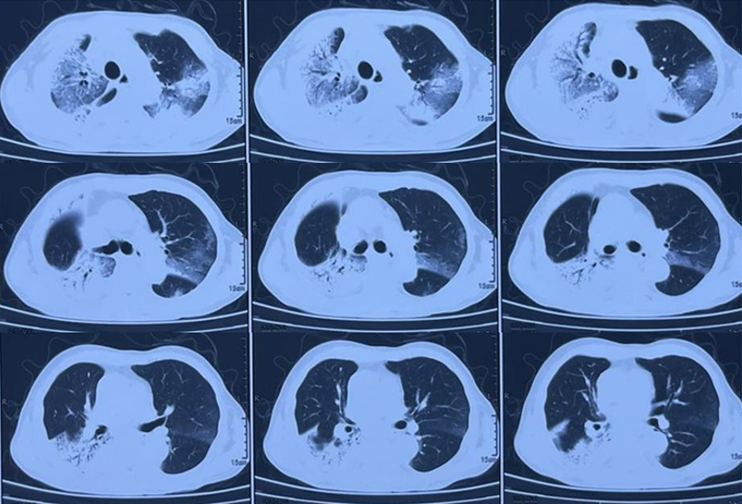

图5为AE-IPF患者的胸部CT,表现为双肺外周带的磨玻璃影,进展迅速。

图5  AE-IPF患者胸部CT

图6为HP患者的胸部CT,广泛的磨玻璃影,夹杂小叶中心结节。

图6  HP患者胸部CT